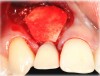

Case 3: Congenitally missing lateral incisors at the sites of teeth Nos. 7 and 10. Both sites were treated simultaneously. (Treatment at the site of tooth No. 10 is illustrated.)

Figure 19

Fig 20. Papillae-sparing incisions were developed both horizontally and vertically. The pedicle flap was elevated, exposing a thin ridge.

Figure 20